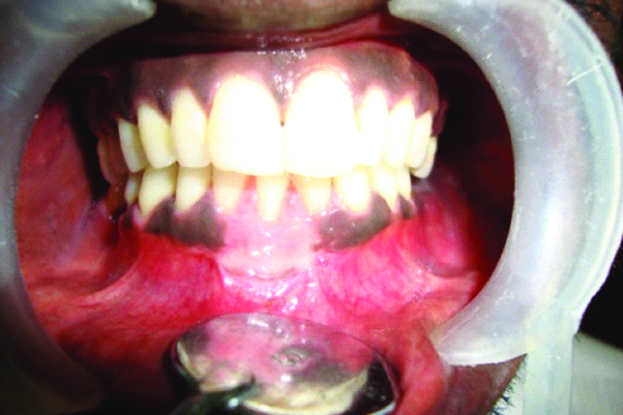

Six months postoperative photograph of #41 region.

Studies done in the past using FGG technique have reported a coverage of 40-70% in Class I and II recessions but the relative inadequacy of interdental papilla, as well as the position of the tooth as seen in Class III recession, can result in incomplete root coverage [7,8,9]. However, in the present case, we could achieve a 100% root coverage. Postoperatively, three months after the surgery, there was 7 mm of root coverage that also lead to a gain of 7 mm of WKT which was the same even at the sixth month [Table/Fig-8]. To measure it in an objective way, we used RES, a standardised system for aesthetic evaluation after root coverage which was introduced by Cairo F et al., and has been used widely in many RCTs [10]. The RES scores for the present case were 100% at third and sixth months for all parameters except for gingival colour [Table/Fig-9]. These results resonated with studies done by Yucea BH et al., and Cortellini P et al., wherein the scores were favourable in terms of mucogingival alignment, soft tissue texture but unfavourable in terms of colour match [11,12]. Also, there was a significant reduction in dentinal hypersensitivity postoperatively as reported by the patient.

Even though good colour match was unachievable, nevertheless, the patient was rationally happy, as the aesthetic discrepancy was considerably reduced. The main reason for the mismatch in colour could be deep melanin pigmentation in gingiva in the present patient, where race factor plays a pivotal role. Some studies have reported that grafted tissue might retain a few characteristics of the donor site and the melanisation might reappear after six months [13]. However, the patient did not turn up after the follow up at six months, so we could not draw any conclusion regarding the colour match as well as photographic evidence of the operative site.